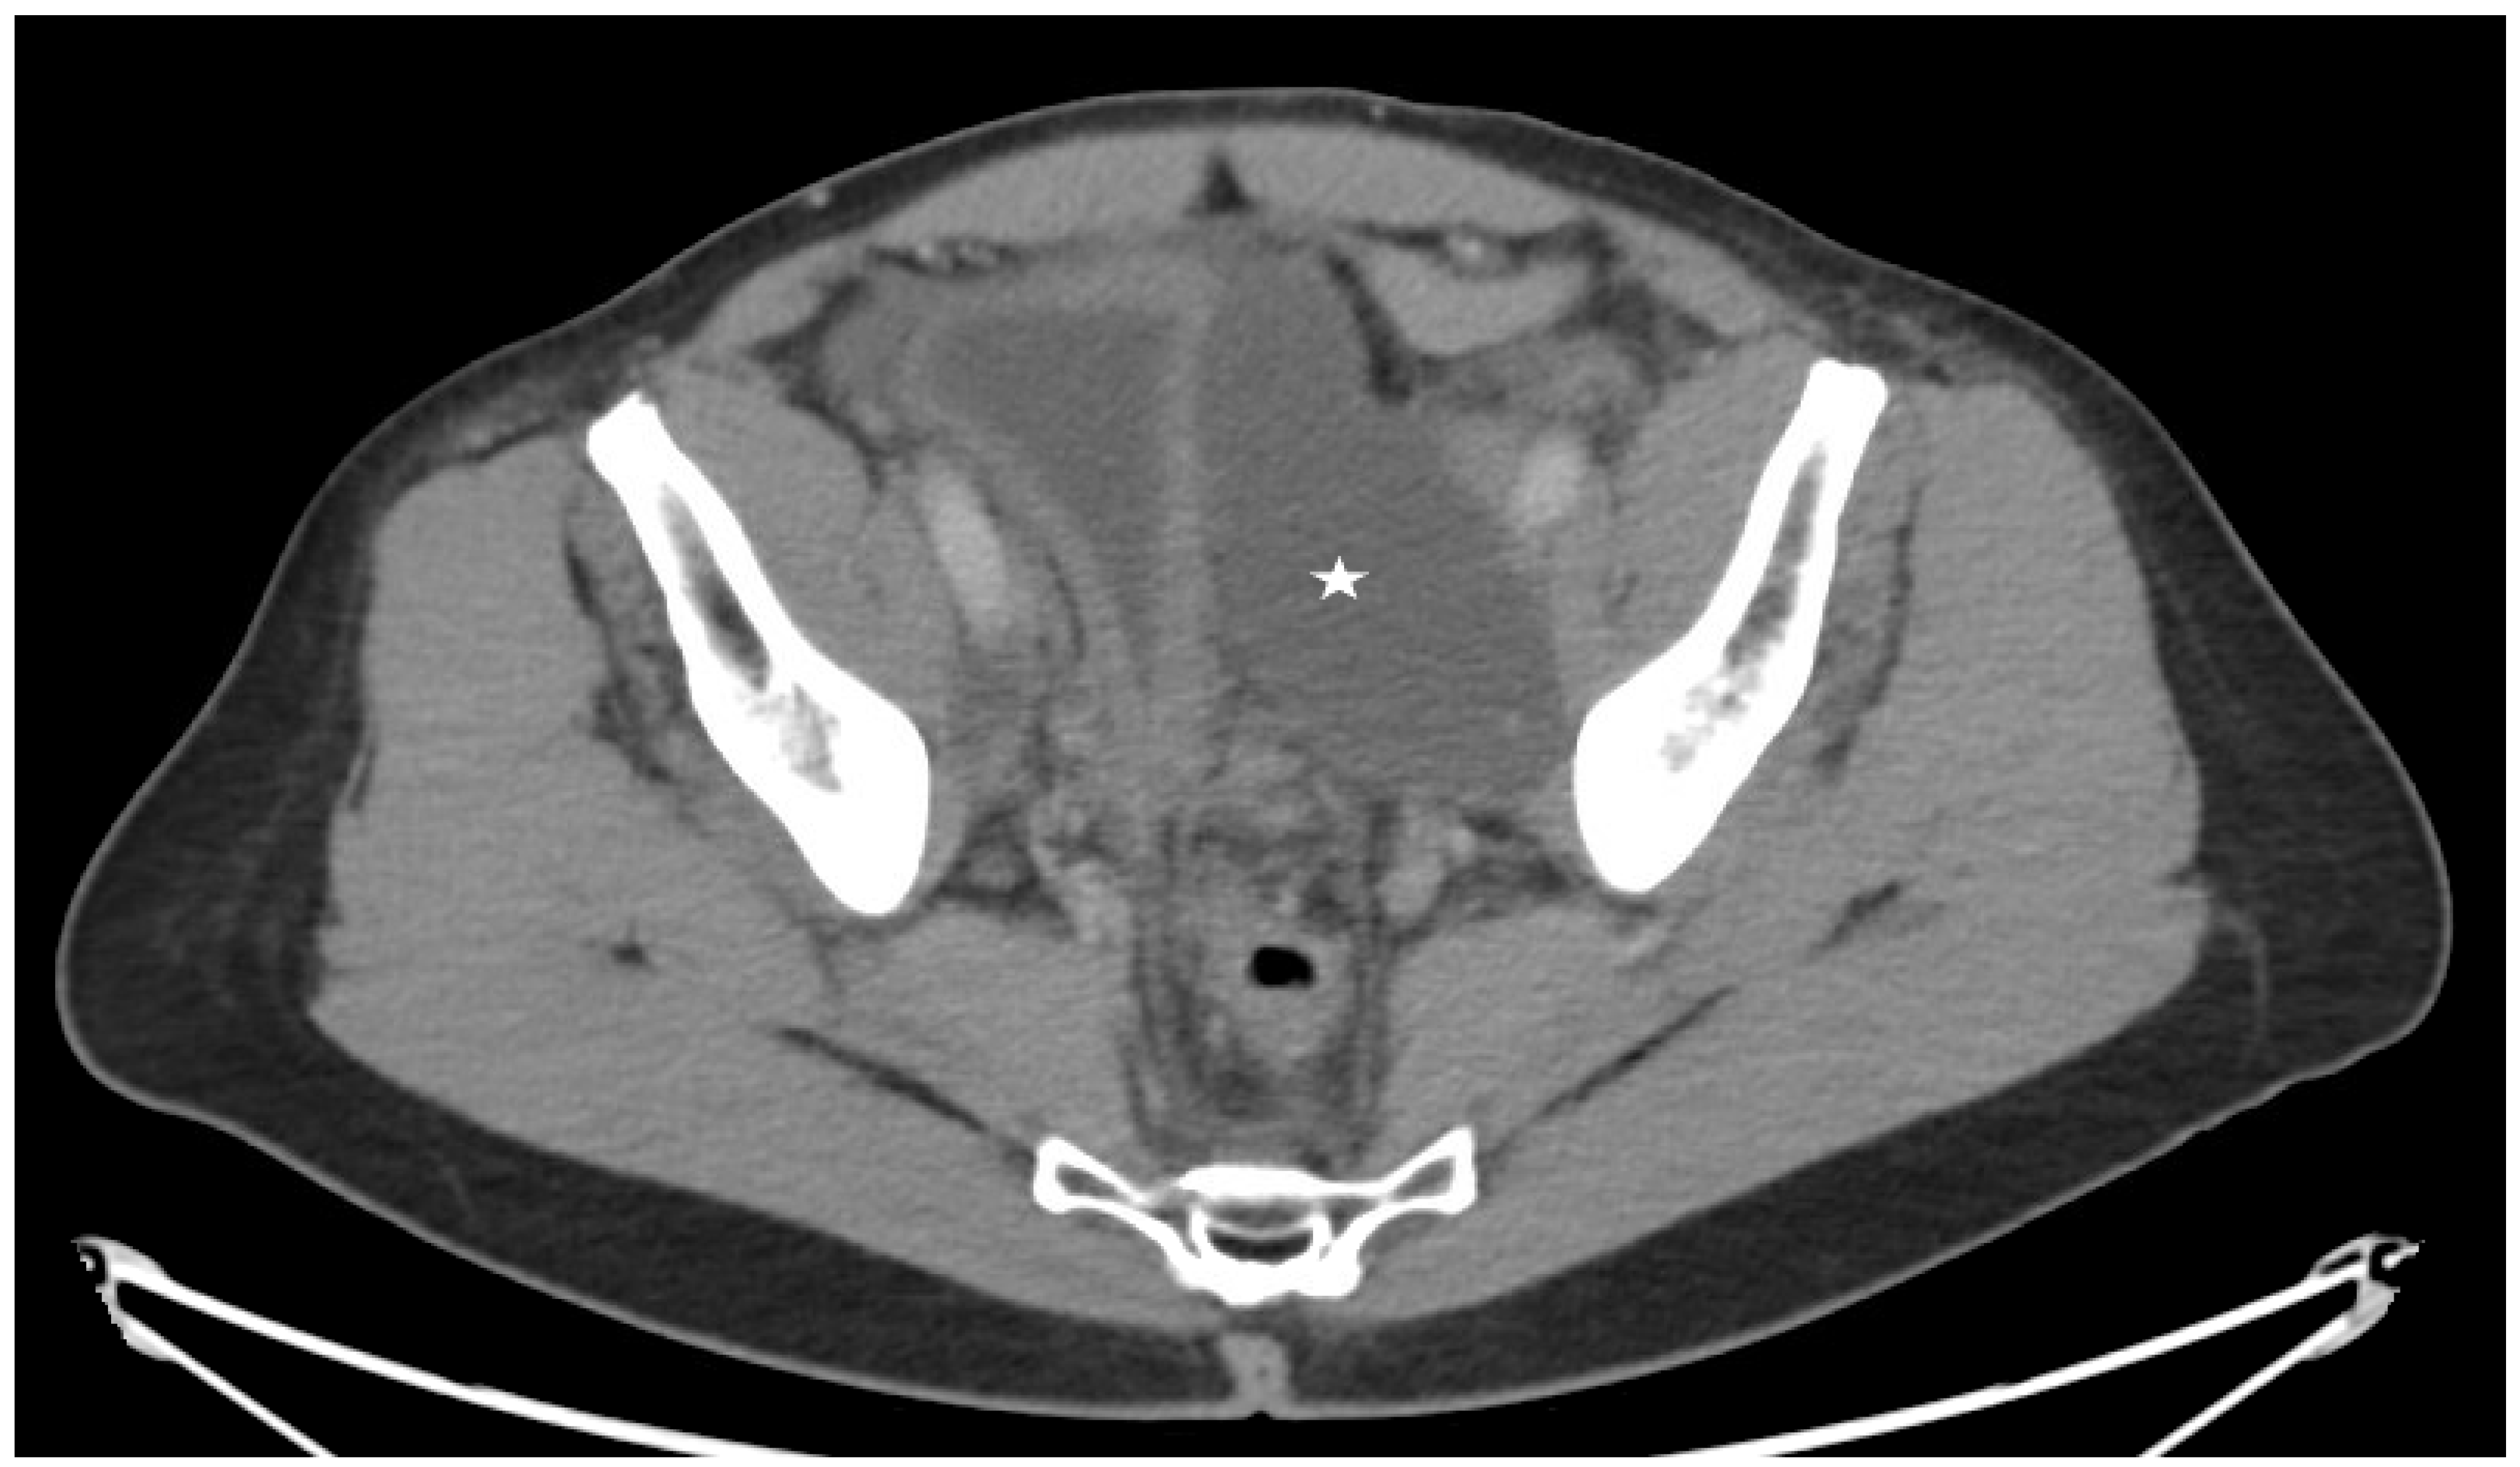

Figure 5.

Axial cut from a Computed tomography of the pelvis for a 65-year-old patient with a left pelvic lymphocele (star) after prostatectomy and pelvic lymph node dissection.